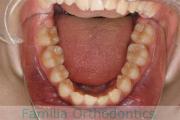

No.14V-516

- 主な症状:

- 上顎前突

- その他の症状:

- 叢生

- 年齢:

- 10歳

- 性別:

- 女性

- 抜歯部位

- 上:

- 44

- 下:

- 55

- 主な使用装置:

- FEA

- 治療にかかった費用:

- 90万円

きれいな歯並びにしたいということで来院されました。第一期治療で六歳臼歯の位置を維持する装置を入れて第二期治療の準備をしました。第二期は中学生になってから小臼歯を抜歯して行いました。二期治療は約2年半、25回程度の通院が必要でした。

- ≫治療後

二期治療開始前は叢生(でこぼこ、凹凸、ガタガタ)がかなりありましたので、保定をしっかりしないと段差ができてきたり後戻りのリスクがあります。